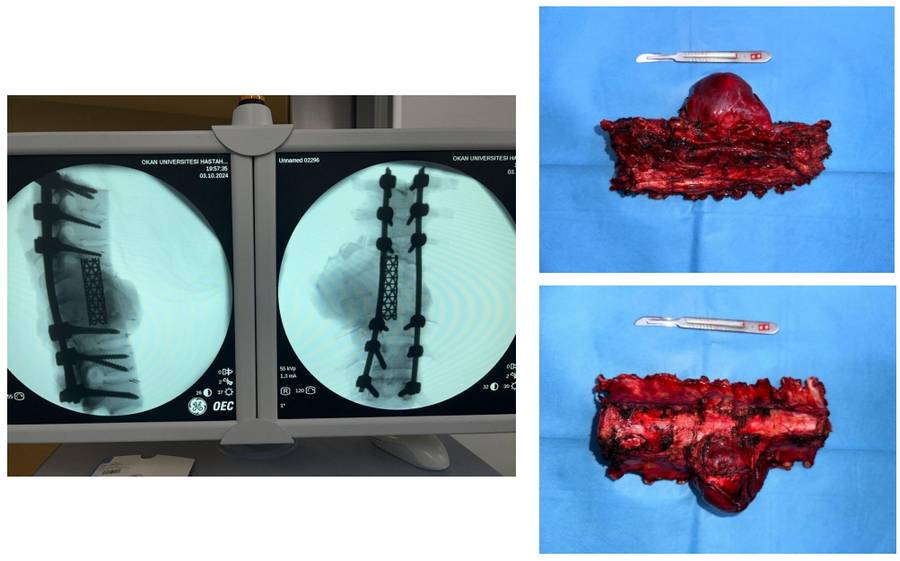

Ameliyat esnası: Korpektomi sonrası fibula, cage ve enstrümentasyon uygulaması ve yaranın kapatılması görülmekte

Ameliyat esnası: Çıkarılan omurgaların klinik ve skopi görüntüleri